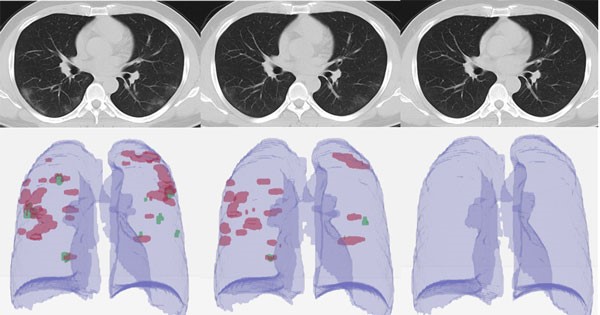

در علم پزشکی به این لکهها، کدورت شیشه مات (Ground-glass opacity) گفته میشود. فردی که به این ویروس مبتلا نباشد، رنگ ریههایش در سی تی اسکن کاملا سیاه است

لکههای به وجود آمده در نتیجه آزمایش سی تی اسکن بیمار مبتلا به کرونا نشان دهنده ایجاد مایع در ریههای فرد و درگیری آنها با ویروس است. حال میزان درگیری ریهها به تشخیص پزشک معالج فرد مبتلا اعلائم میشود.